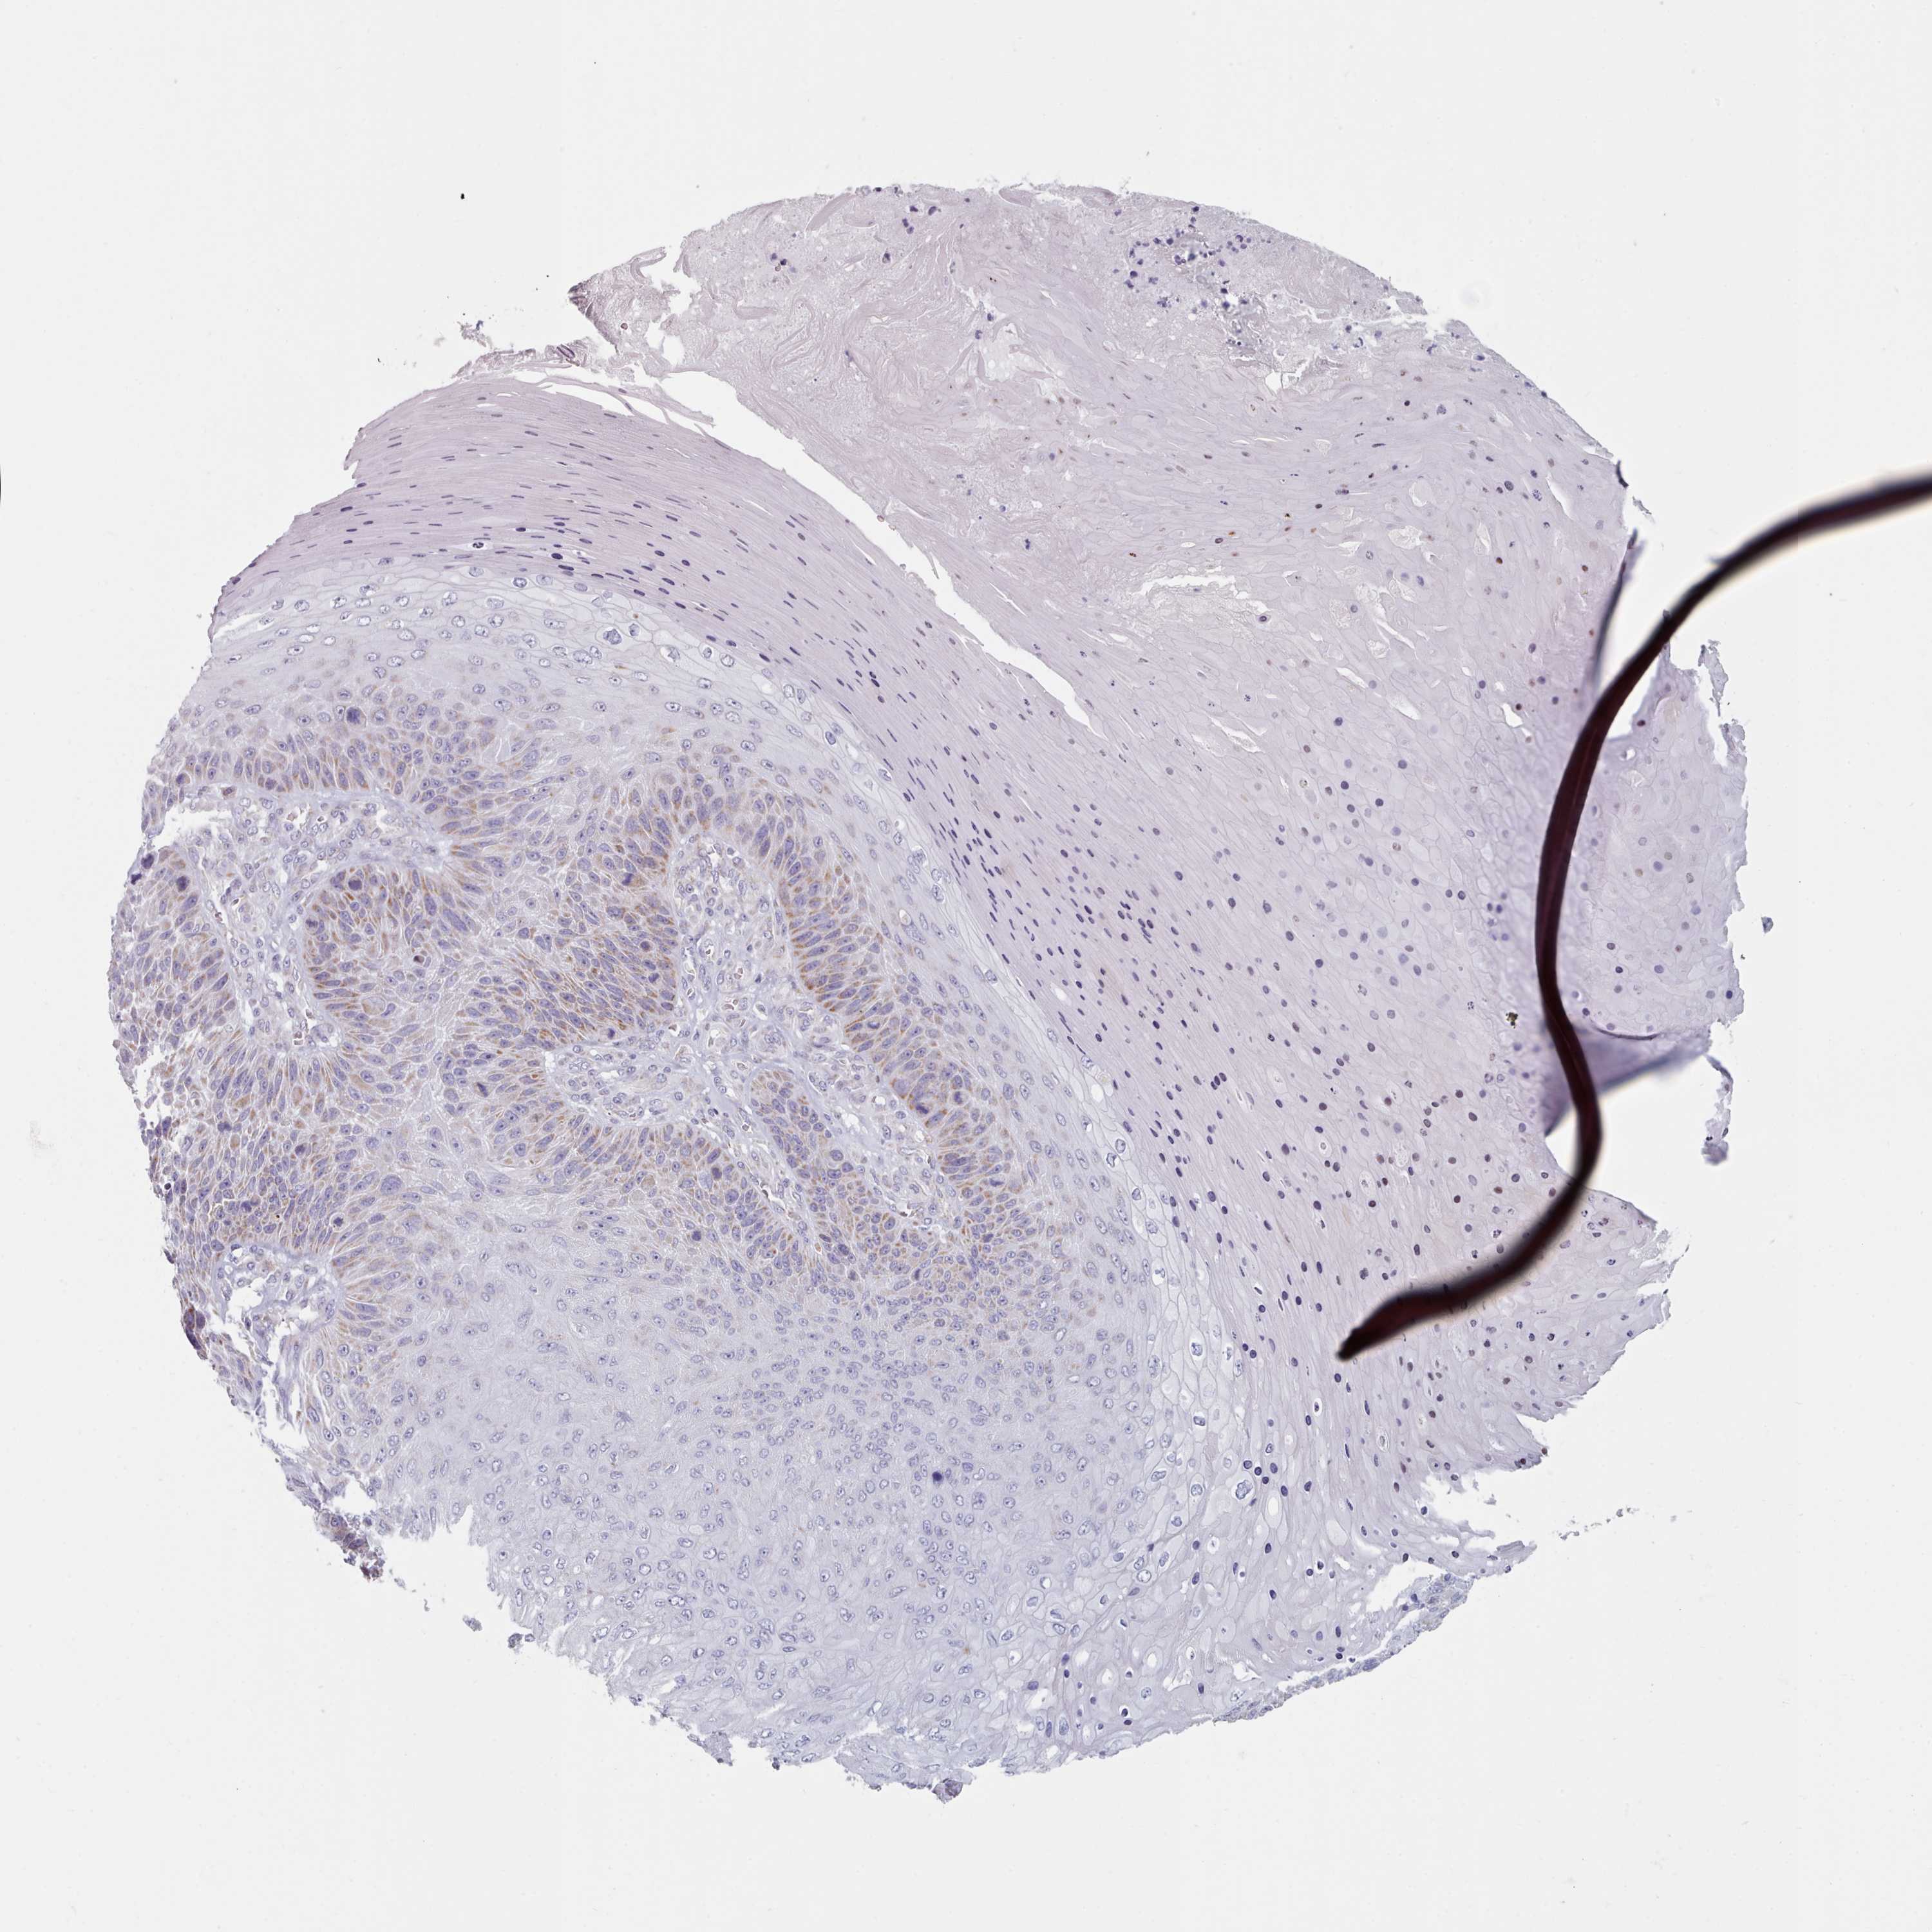

CANCER SKIN CANCER Show tissue menu

Basal cell and squamous cell cancer

SKIN CANCER - Protein expressioni

A mouse-over function shows sample information and annotation data. Click on an image to view it in a full screen mode. Samples can be filtered based on level of antibody staining by selecting one or several of the following categories: high, medium, low and not detected. The assay and annotation is described here.

Each image is clickable and will lead to virtual microscopy that enables deeper exploration of all samples and also displays staining intensity scores, fraction scores and subcellular localization as well as patient and tissue information for each sample.

Antibody HPA043899

Basal cell carcinoma